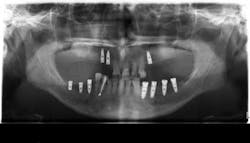

The third article is titled “Peri-implant Hard and Soft Tissue Stability in Implants Placed Simultaneously Versus Delayed with Intraoral Block Bone Grafts in Horizontal Defects: A Retrospective Case Series Study.” In this retrospective case series, investigators from the University of Valencia, Spain, compared the three-year outcome of dental implants placed simultaneously or delayed with intraoral onlay block bone grafts before or at implant placement between 2005 and 2010. The parameters evaluated at follow-up visits were implant survival and success rates, peri-implant soft-tissue conditions (Plaque Index and Bleeding Index, probing depth, width of keratinized mucosa, and facial mucosal retraction), radiographic peri-implant marginal bone loss, and patient satisfaction. Thirty-four patients with 53 implants (23 delayed and 30 simultaneous) were included.

After three years of loading, the cumulative implant success rate was 83.3% for simultaneous and 96.9% for delayed implants (P = .217). Average marginal bone loss was 1.15 ± 1.67 mm for simultaneously inserted implants and 0.29 ± 0.35 mm for delayed implants (P < .01). There were no significant differences in Plaque Index or modified Bleeding Index between the groups. Peri-implant facial mucosal recession was more frequent in the simultaneous implant group (26.6% vs 13%), though the difference was not statistically significant. General patient satisfaction averaged 9.05 ± 0.82, and good quality of life was reported by all patients.

The authors concluded that despite its sample size and design limitations, the delayed procedure showed less marginal bone loss and a lower prevalence of facial mucosal recession than the simultaneous implant placement procedure at three years post-loading.